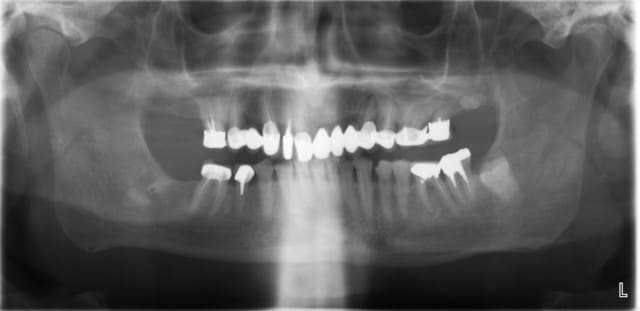

36 et 37 toutes les 2 fêlées ont été extraites, comme 24.

patient de 72 ans en bonne santé, j'ai carte blanche...

-au max : ext, implantation, MCI

-à la mdb : impl 36, rett endo 45 46, ccm partout ( perte de dv ~3 mm )

ps: 27: la racine est quasi à l'horizontale ou quoi?

28: il semble rester un truc par là, à surveiller au moins.

48 incluse: à surveiller et peut être pas obligatoirement à extraire si tu places implant en 46 car elle sera à distance mais pense au cas où tu devrais l'extraire 1 de ces 4 alors que les protheses seront en place.... peut être envisager intervention en 1 temps, pose implant et extraction 48?

tu veux parler de 38 ? j'espère ne pas avoir à l'extraire ( j'ai galéré un max pour ext 36 37 ).

pour ce qui est de 27, comme 26, les raçines sont fracturées ; je pense les extraire dans un 1er temps.

28 est là sans bouger depuis 50 ans ; je croise les doigts